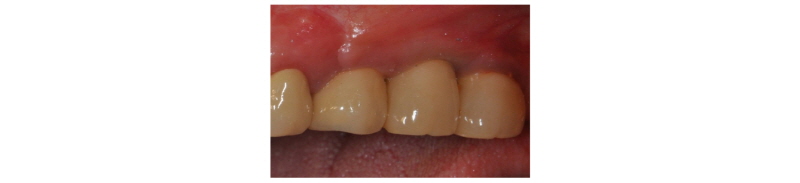

Fig. 16. Clinical clinical view. Final prosthesis. |

Fig. 17. Panoramic x-ray view. Final prosthesis. |